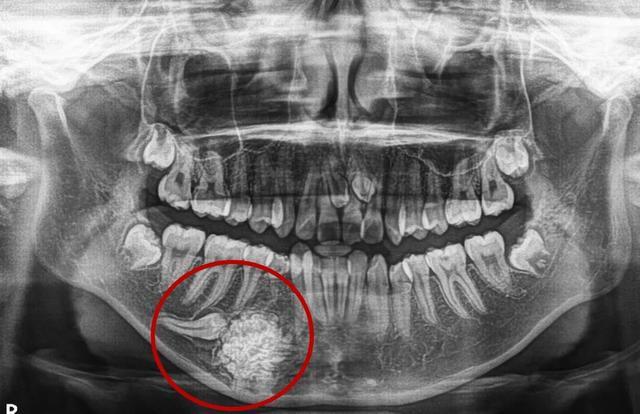

庞大的多生牙组合体--牙瘤

750x422 - 38KB - JPEG

640x360 - 22KB - JPEG

【原创博客】罕见的巨大牙瘤

560x414 - 132KB - JPEG